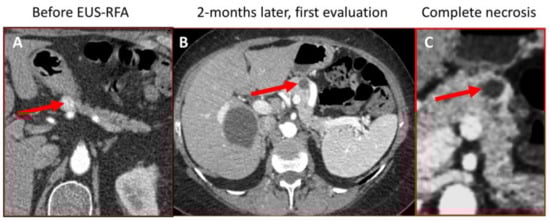

3.2. Focal Control and Survival